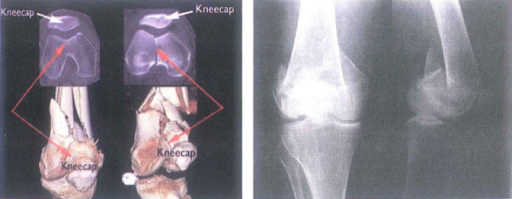

Hình 8.6. X-quang và CT dựng hình gãy trên và liên lồi cầu xương đùi

- X-quang: Hình ảnh gãy trên lồi cầu đơn thuần, gãy liên lồi cầu đơn thuần hoặc phức hợp cả 2.

Hình 8.7. A. Gãy trên lồi cầu đơn thuần, B. Gãy liên lồi cầu đơn thuần, c. Gãy phức hợp cả hai (Ronald McRae, 2008)